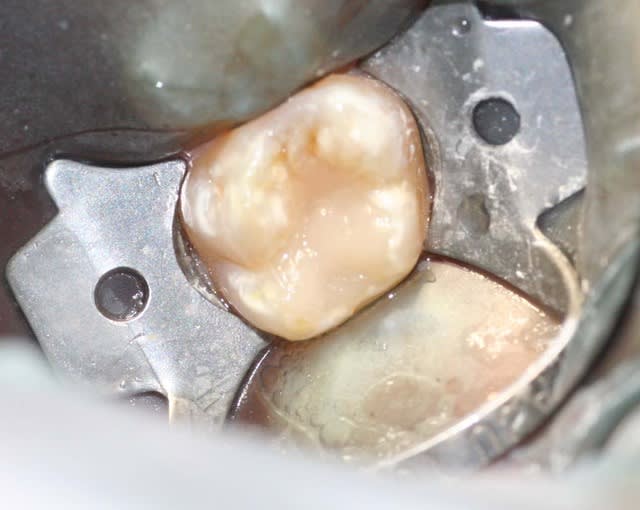

en parlant de compo, je sais que je suis pas au niveau des maitres du forum, mais ce matin je me suis un peu amusé.